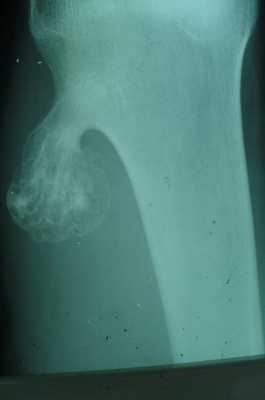

Остеохондрома

- кроме костной ткани содержит и хрящевую, покрывающую поверхность опухоли в виде шляпки,

- исходит из плечевой кости, из мета-эпифизов в области коленного сустава, в головке малоберцовой кости, грудной отдел позвоночника(исходит из дужек или отростков),

- опухоль сидит на широкой ножке и возвышается на кости в виде цветной капусты.

- поверхность ее бугристая, контуры резко очерчены,

- корковое вещество кости переходит на поверхность опухоли или выступает в середину нароста, рассыпаясь на отдельные костные прослойки, идущие в виде лучей к поверхности опухоли,

- рисунок ее не гомогенен, состоит из костных островков, веерообразных пучков и перегородок, лежащих среди светлого фона хряща,

- остеохондромы обладают высоким потенциалом озлокачествления.

Остеохондрома. Остеохондрома — одиночная, в редких случаях — множественная опухоль, состоящая из костной и хрящевой ткани. М. В. Волков отмечает, что разница между хондромой и остеохондромой — количественная в смысле степени оссификации опухоли.

М. В. Волков считает, что под остеохондромами именуются обызвествившиеся хондромы. «Когда речь идет об остеохондроме, чаще всего подразумевается оссифицирующая хондрома, хондрома с известковыми включениями». С подобной точкой зрения согласиться нельзя. Морфологическая картина истинных остеохондром описана Т. П. Виноградовой. Наши клинико-рентгенологические наблюдения выявили определенные различия в картине хондром и остеохондром. Остеохондромы, в отличие от хондром, преимущественно локализуются в длинных трубчатых костях (медиальная поверхность проксимального метафиза плечевой кости, дистальный метафиз, эпифиз бедренной кости, проксимальный метафиз большеберцовой и проксимальный метафиз, эпифиз малоберцовой кости и др.) и соединены с основной костью ножкой. Из плоских костей чаще других поражаются лопатка, ребра, кости таза. Остеохондрома может исходить из отростков позвонков и мелких костей.

Наши данные подтверждают имеющиеся в литературе сведения о преимущественной локализации остеохондром в длинных трубчатых костях и лопатке. Указанные локализации для хондром являются редкостью.

Рентгенологическая картина остеохондром достаточно типична. Однако нельзя полностью согласиться с описанием остеохондромы, представленной в руководстве С. А. Рейнберга «Остеохондрома лишь мало отличается от остеомы: она кроме костной содержит еще хрящевую ткань, покрывающую поверхность опухоли в виде шляпки». Подобное описание характеризует юношеские костно-хрящевые экзостозы (дисплазия).

Остеохондрома на рентгенограмме представлена в виде дополнительной тени, соединенной с костью ножкой или реже — широким основанием. Растет в сторону от сустава, медленно, но может достигать больших размеров. Контуры остеохондромы бугристые, неровные. Кортикальный слой в виде тонкой окаймляющей пластинки прослеживается на всем протяжении опухоли. Иногда корковое вещество лучеобразно направлено к поверхности опухоли. Обращает внимание сочетание мелких участков деструкции (хрящевая ткань) с наличием трабекулярного рисунка и массивных вкраплений известковых теней. При больших размерах остеохондром наблюдаются деформации соседних костей. Например, выраженное искривление и деформация кортикального слоя малоберцовой кости при больших размерах остеохондромы большеберцовой кости. Мы наблюдали также раздвигание и деформацию ребер при остеохондроме ребра у ребенка 11 лет.